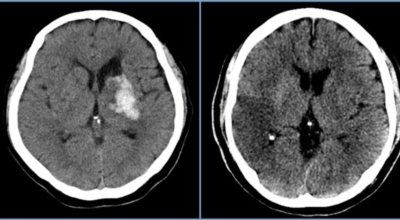

파킨슨병이라고 하는 것은, 퇴행성 뇌 질환으로 알츠하이머, 치매 다음으로 빈번히 나타나는 뇌 연관 질병으로 1817년 영국 병리학자 파킨슨이 보고 해서 그의 이름을 따서 병의 이름이 결정되었다고 합니다.파킨슨병에 걸릴 경우 대부분이 40세 이후로 첫 증상이 나타나고 50세에 가장 많이 발생한는 것으로 알려져 있으며 30세 이전에는 아주 드물지만 유전적으로 나타나는 경우도 있다고 해요.

파킨슨병은 도파민 분비 신경 세포의 소실로 발생하는 질환으로 알려져 있는데요 도파민이란 뇌의 신경세포에서 만들어지는 물질로 세포와 세포 간의 신호를 전달하는데 이용되는 신경 전달 물질 중 1개로 이 도파민이 감소함에 따라 파킨슨병이 걸린다고 하는데 이 도파민 세포가 떨어지는 이유는 아직 정확히 알려지지 않았다고 합니다. 일부 파킨슨 환자는 파킨슨병의 가족력이 있는 경우가 있으며 이런 가족들 중 일부에서는 유전자 이상이 발견되기도 해요.